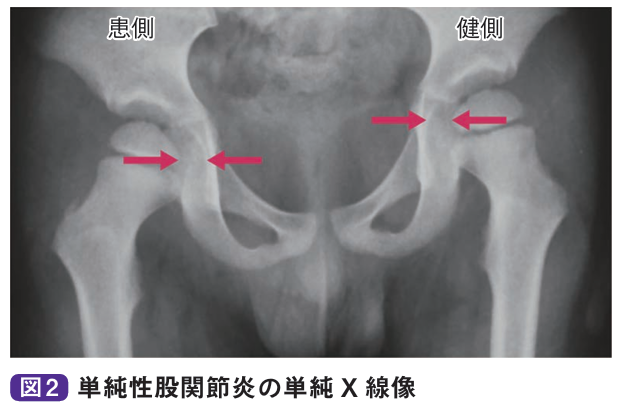

診察とレントゲン、エコーなどで診断します。関節可動域は軽~中等度と制限され、とくに屈曲位で内旋が制限されます。微熱を認めることがありますが、通常、血液所見は正常値を示します。単純X線像では関節液の貯留により関節包陰影の膨隆、関節裂れつ隙げきの開大、骨頭の外方化などを認めますが、骨陰影に異常を認めません。超音波検査やMRI検査で関節液貯留が明らかとなります。